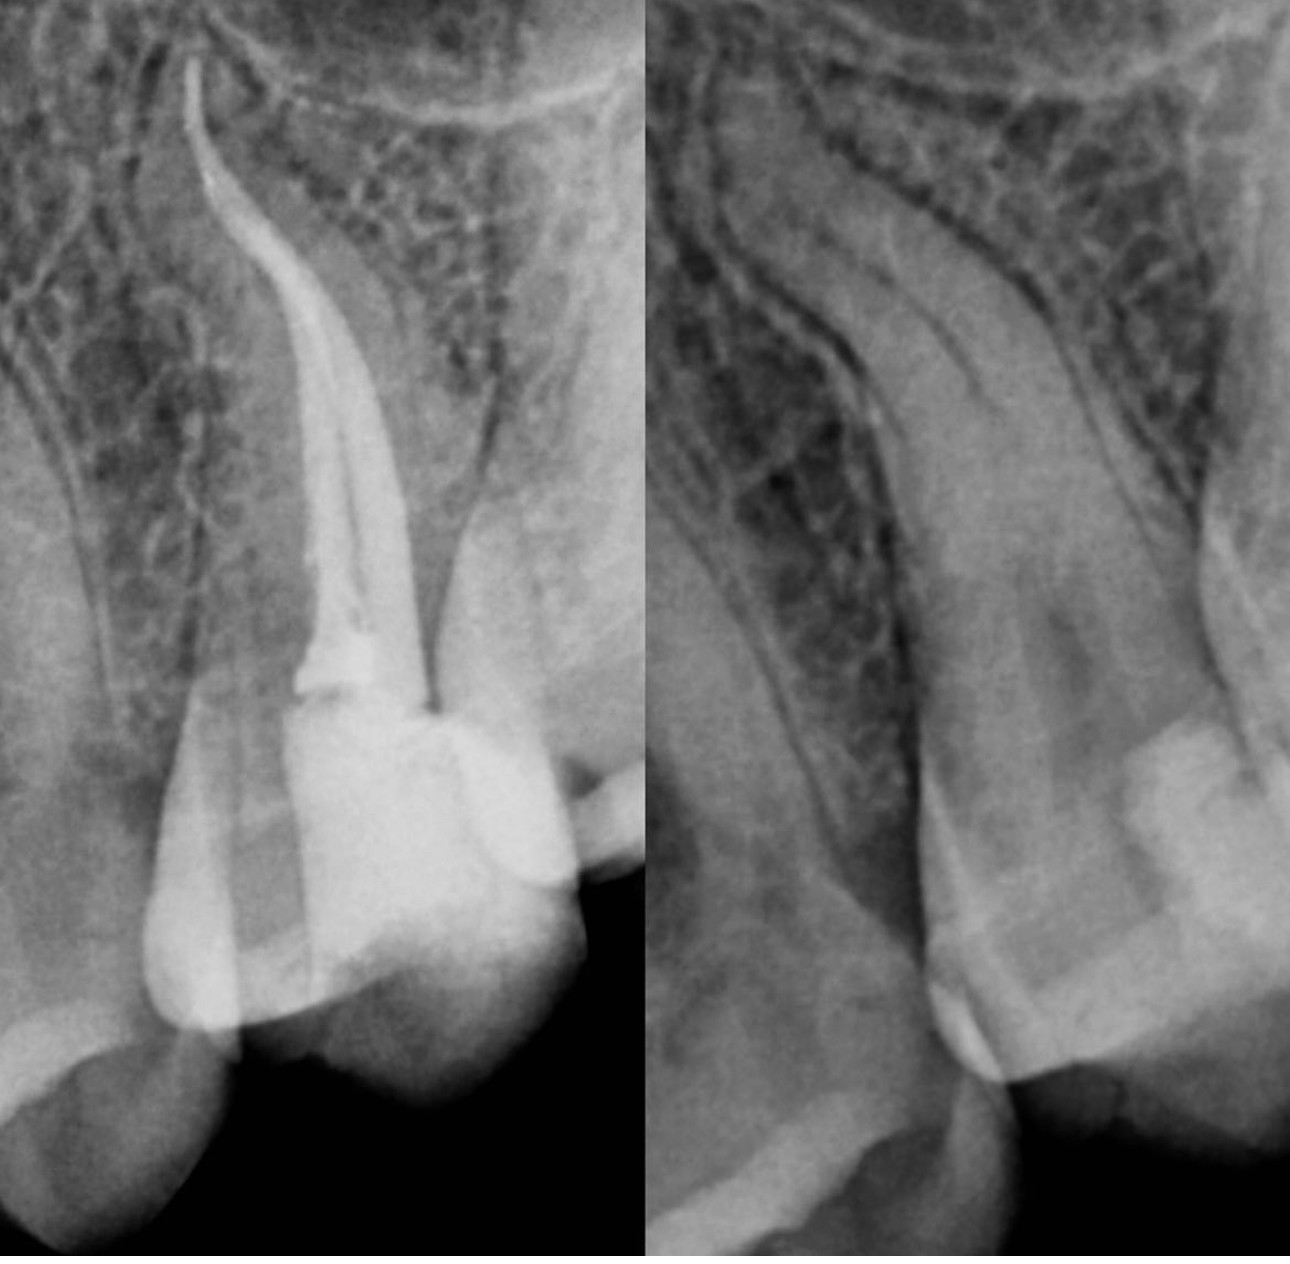

3. Evaluate the root canal treatment of tooth # 1.7?

4. Evaluate the root canal treatment of tooth # 3.6?